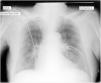

Paciente de 86 años de edad que ingresa en nuestra unidad tras realización de intervencionismo percutáneo urgente por infarto agudo de miocardio con elevación del ST de cara anterior con implante de 2 stents farmacológicos en DA y 1.a diagonal. A su ingreso en situación hemodinámica y respiratoria estable con saturación de oxigeno por pulsioximetría del 93% sin aporte de oxígeno. Se le realiza radiografía (Rx) de tórax en supino en la que se observan 2 líneas sugerentes de neumotórax bilateral (fig. 1, flechas) que dejan de visualizarse en lóbulos superiores (fig. 1, puntas de flecha). Para descartar el neumotórax bilateral se realiza ecografía torácica bilateral en la que se observa «sliding» pleural e imagen en modo M de «orilla del mar» o «seashore sign» (fig. 2). En una Rx realizada después, en semisedestación, solo se observa una pequeña línea basal derecha (fig. 3), estableciéndose el diagnóstico de falso neumotórax bilateral secundario a pliegue cutáneo.